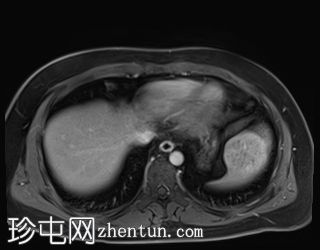

冠状位

T2加权像

T1低信号,T2低信号为主的脾脏肿块,内部可见T2高信号分隔,呈进行性强化。肿块中央可见星状瘢痕。

脾脏硬化性血管瘤样结节性转化(SANT),9.8 cm肿块

顾名思义,脾脏硬化性血管瘤样结节性转化(SANT)是一种纤维性血管病变。本病例展示了SANT的一些典型影像学特征,包括边界清晰的病灶,中央可见瘢痕,以及呈放射状进行性强化。这些特征使得术前MRI诊断较为明确。尽管SANT是一种良性病变,但大多数患者仍需行脾切除术以明确病理诊断。